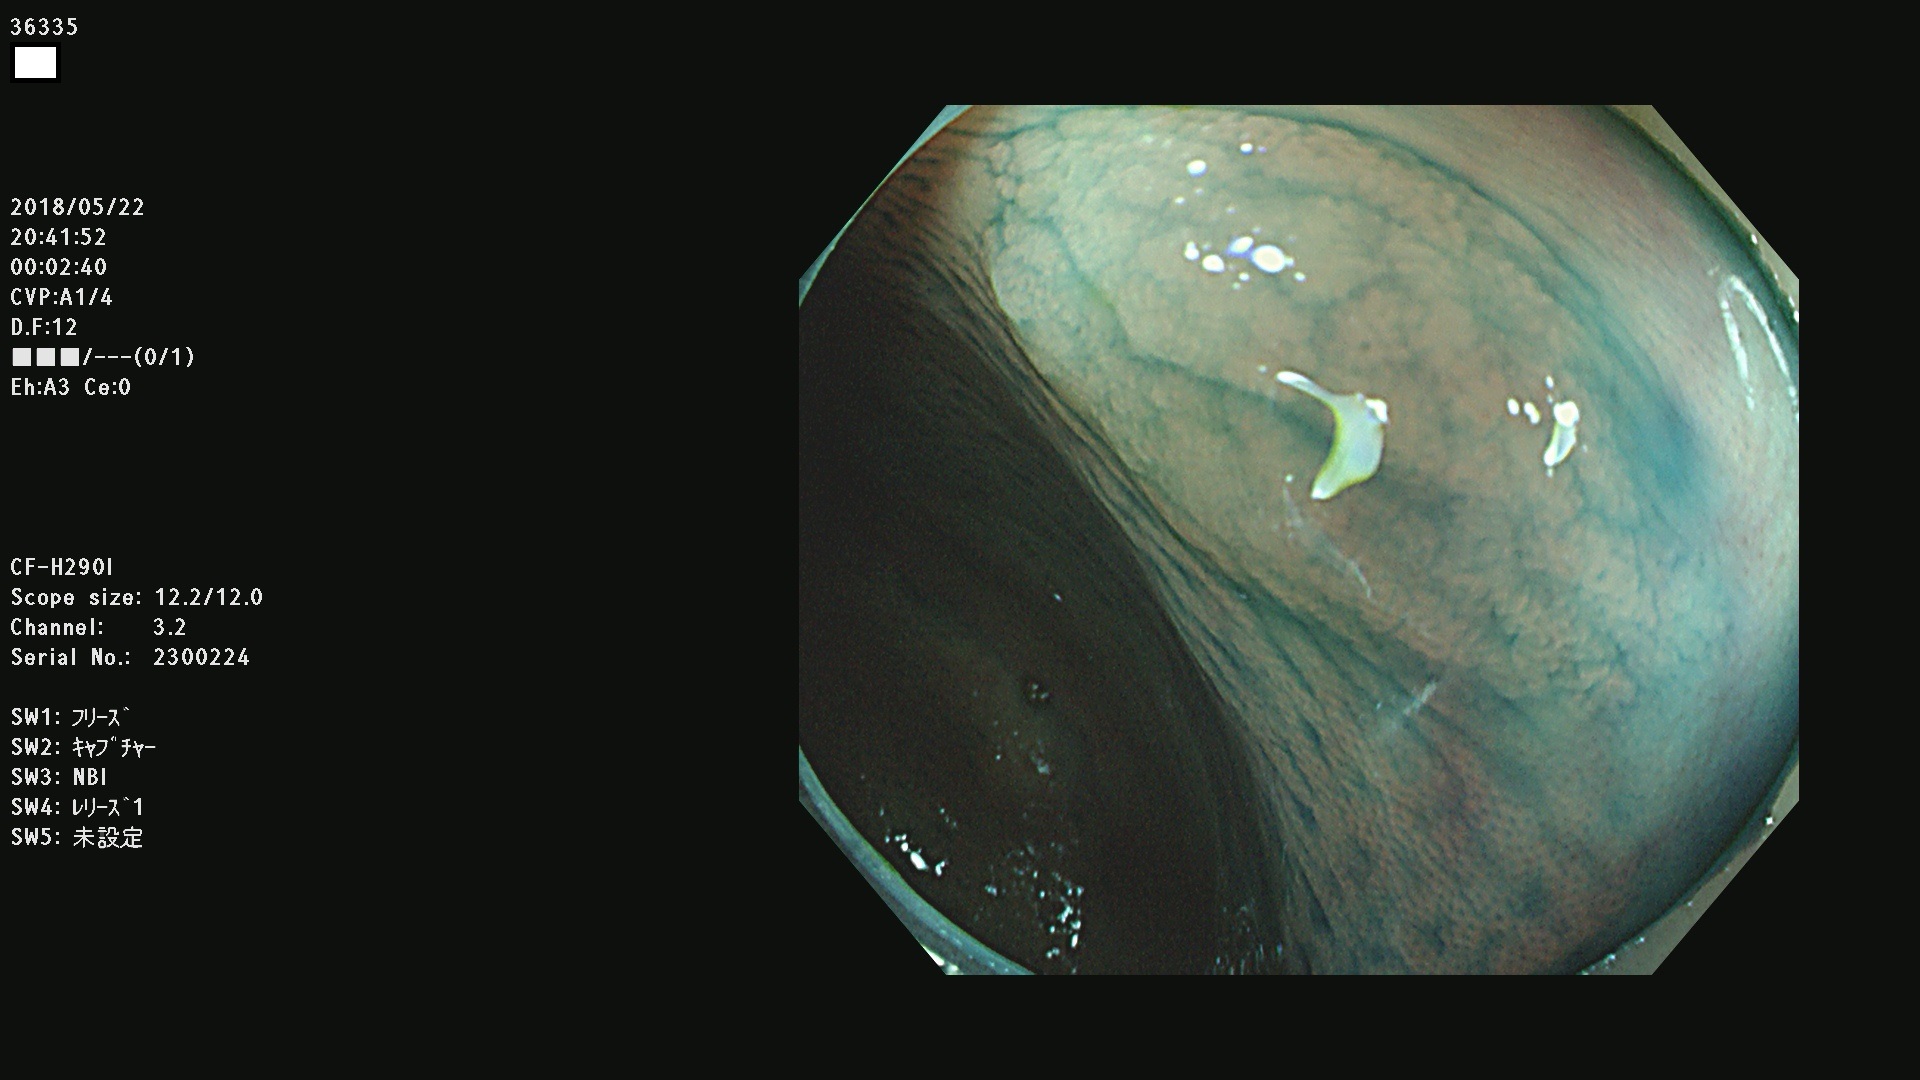

発見困難で危険性の高い平坦型病変(上記100名より抽出) ![]()